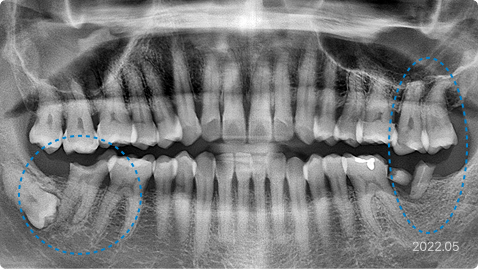

국소마취가 잘 안되는 경우

“치과 치료받을 때마다 마취가 잘 안돼서 걱정돼요.”

치료 전

치료 후

치료 내용

• 어금니가 부서지고 아픈데 치과에서 국소마취가 너무 안돼서 치료를 못 받음

• 의식하진정법(수면마취)으로 안정 후 충분한 마취 하에 하루에 다수 치료

• 수술 후 연결되어 있는 정맥주사로 무통 주사 진통제 투여